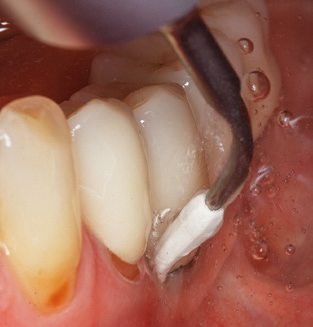

Naturalmente, anche i consigli di lavoro per la pulizia delle superfici degli impianti sono indispensabili per SPT nei pazienti dotati di impianti. L'inserto per la pulizia dell'impianto in questo casoi è caratterizzato dal suo design affusolato ed esagonale. Questo design consente una penetrazione leggera e atraumatica nella tasca perimplantare e mostra buone prestazioni di pulizia (Fig. 7).

Fig. 4: Sonde flessibili con marcature millimetriche sono consigliate per il sondaggio di impianti dentali (ad es. Colorvue Kit PCV11KIT6, HuFriedy). - Fig. 5a e b: Un inserto diritto (1P, W&H Dentalwerk Bürmoos GmbH) è uno strumento adatto per l'uso su tutti i denti naturali. - Fig. 6: Inserti curvi (3Pr / 3Pl, W&H Dentalwerk Bürmoos GmbH) si prestano alla lavorazione di aree difficili da raggiungere del dente e delle superfici radicolari (ad es. Forcazioni). - Fig. 7: L'inserto esagonale conico per la pulizia dell'impianto (1I, W&H Dentalwerk Bürmoos GmbH) consente una pulizia atraumatica ed efficace della superficie della corona e del moncone. - Fig. 8: Le curette in titanio e carbonio sono strumenti adatti per la pulizia manuale delle superfici dell'impianto.